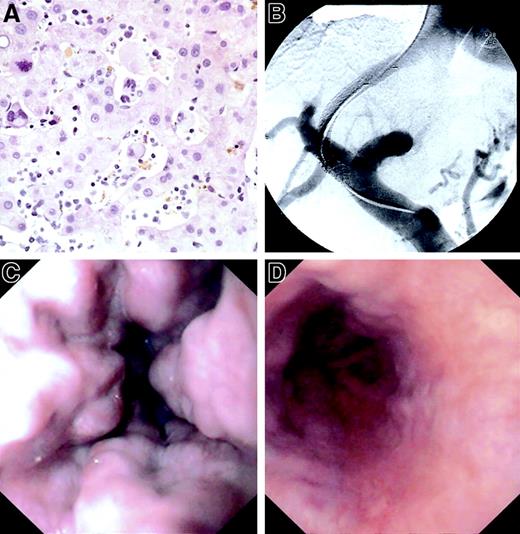

(A) Extramedullary hematopoiesis in dilated sinuses, hematoxylin-eosin staining. Original magnification × 320. (B) TIPS implantation. (C) Oesophagogastroduodenoscopy before TIPS. (D) Oesophagogastroduodenoscopy after TIPS.

The hepatic venous pressure gradient (HVPG) showed portal hypertension with a pressure gradient of 23 mmHg (upper limit of normal, 6 mmHg). A biopsy specimen of the liver showed noncirrhotic liver parenchyma with normal architecture, discrete portal fibrosis, and massive infiltration of the liver sinusoids with hematopoietic cells (Figure 1A).

Since sinusoidal obstruction by extramedullary blood-forming units is not very different from other forms of intrahepatic portal hypertension and conservative treatment (dietary sodium restriction and high-dose diuretic therapy were unsuccessful), we decided to implant a GoreTex-coated TIPS endoprosthesis (Viatorr, W. L. Gore and Associates, Flagstaff, AZ; diameter: 8 mm, length: 80 mm) (Figure 1B), which shows a much improved patency rate compared with previous uncoated TIPS models (80%-100%, versus 50%, at 1 year).7 The reduction of the HVPG to 14 mmHg was followed by a rapid and lasting relief of ascites and a marked regression of the oesophageal varices (Figure 1D). At 6 months after implantation, the patient was free of ascites but still required moderate doses of diuretics because of the residual portal hypertension (ideal HVPG after TIPS is below 12 mmHg).